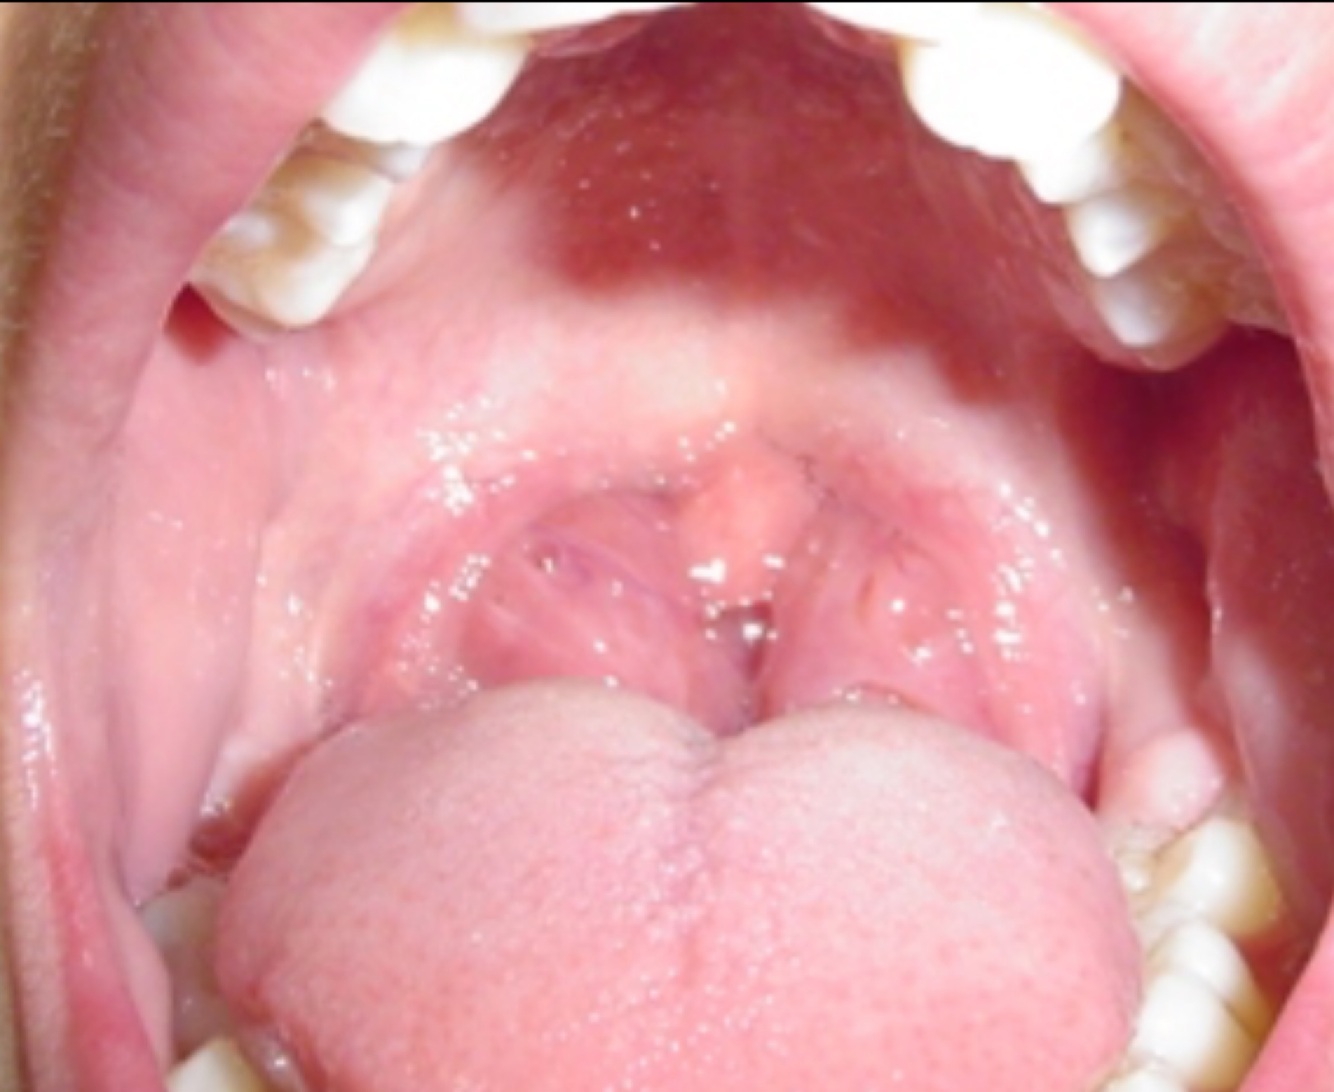

Q

DX

A

Amigdalitis bacteriana

amigdalitis bacteriana o suprativa